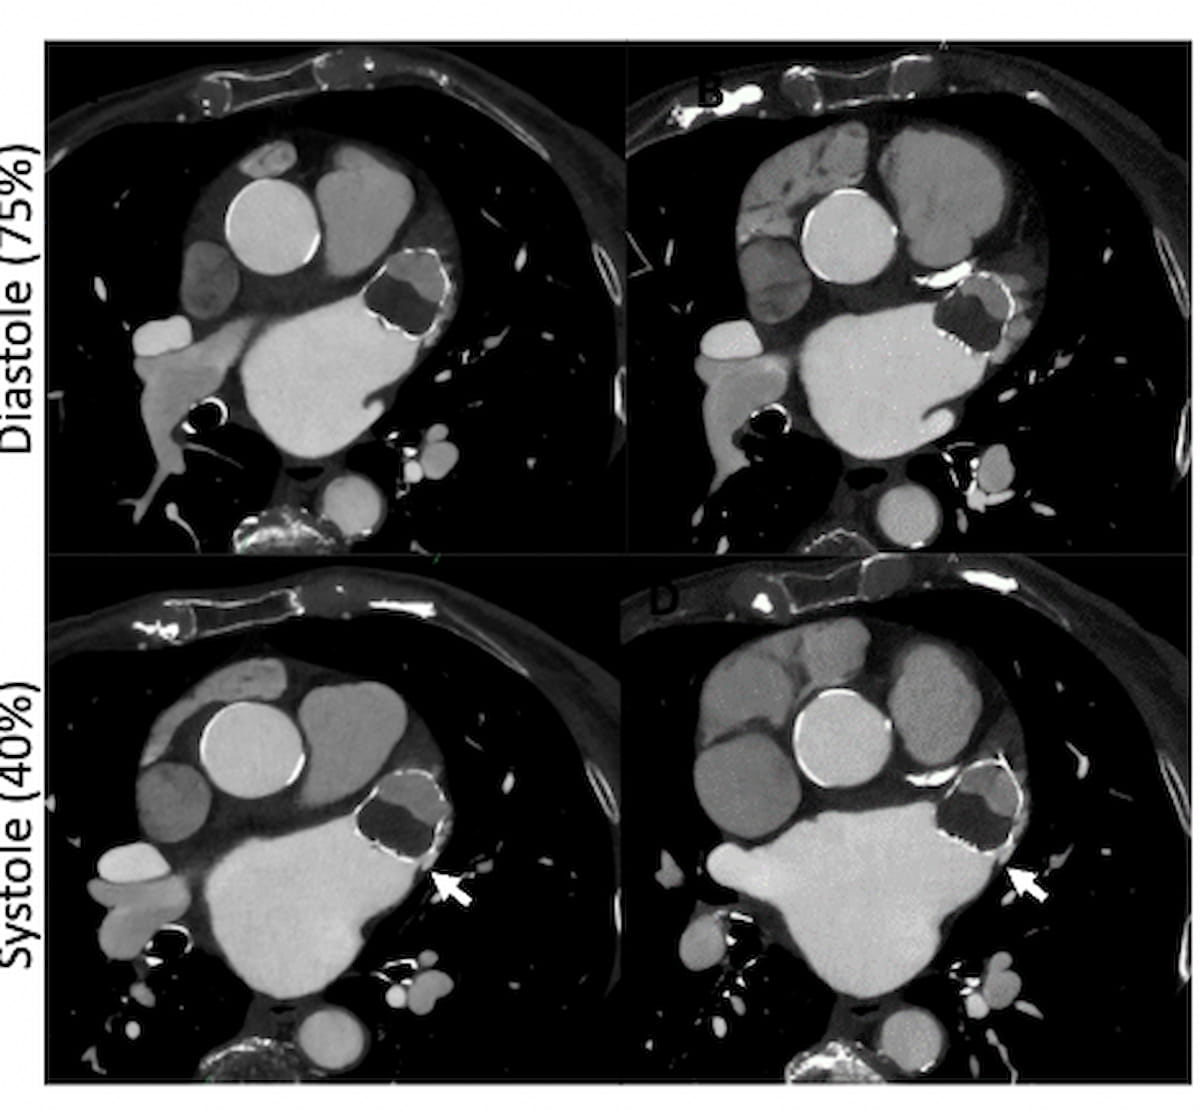

Approximately 45 to 60 days after placement of the Watchman device for LAA closure in some patients with non-valvular atrial fibrillation, the researchers recommended the use off CCTA images near end-systole, subsequent multiplanar reconstruction (MPR) and short axis plane rotation to determine the presence of leaks in the long axis.

Defining a peri-device leak as a contrast enhancement trail on CCTA that is adjacent to the Watchman device, the researchers noted that while peri-device leaks < 5 mm may spontaneously resolve with endothelialization, leaks > 5 mm require the use of oral anticoagulation therapy.